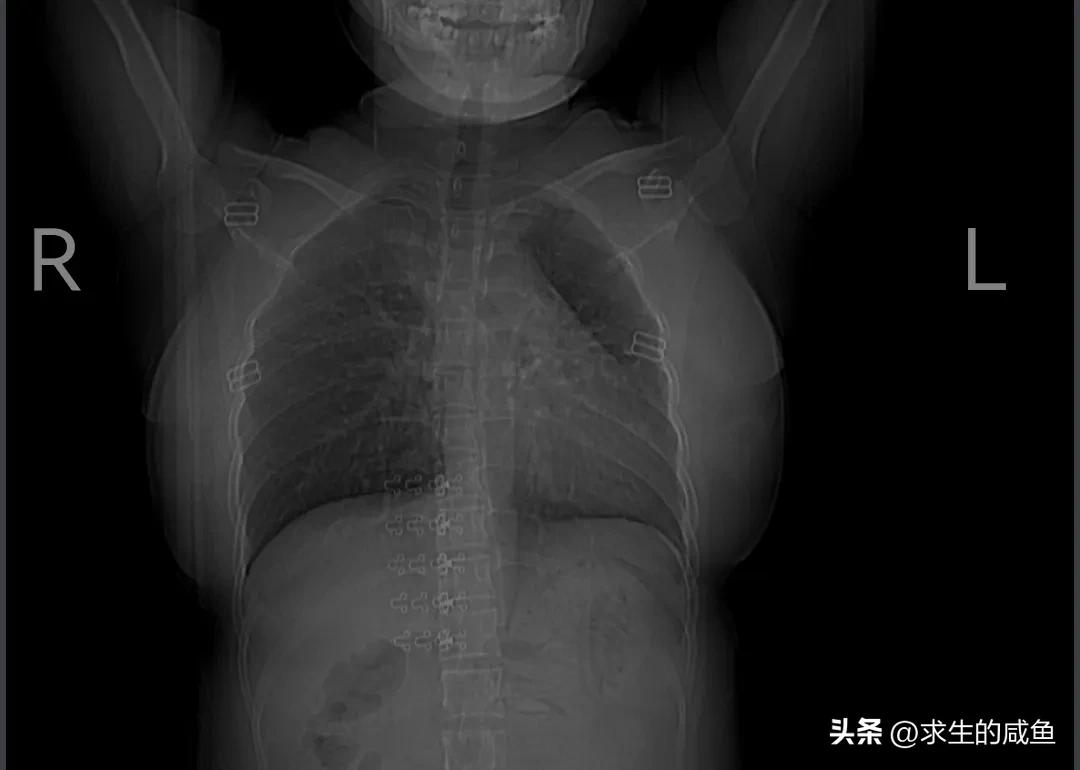

前段时间感觉胸闷乏力,一直有点咳嗽,于是7月3日去医院拍了一个胸部CT检查,花了我213元。结果出来后,提示左肺感染性病变,双侧腋窝淋巴结增多,医生建议我住院打一个星期的消炎针。于是我去办理入院手续并预缴了1000元。

肺部有阴影

住院第一天做了各种化验检查,大部分结果还好,考虑肺部感染以慢性炎症为主,注意定期复查。还有窦性心动过速,医生建议我多做些有氧运动!